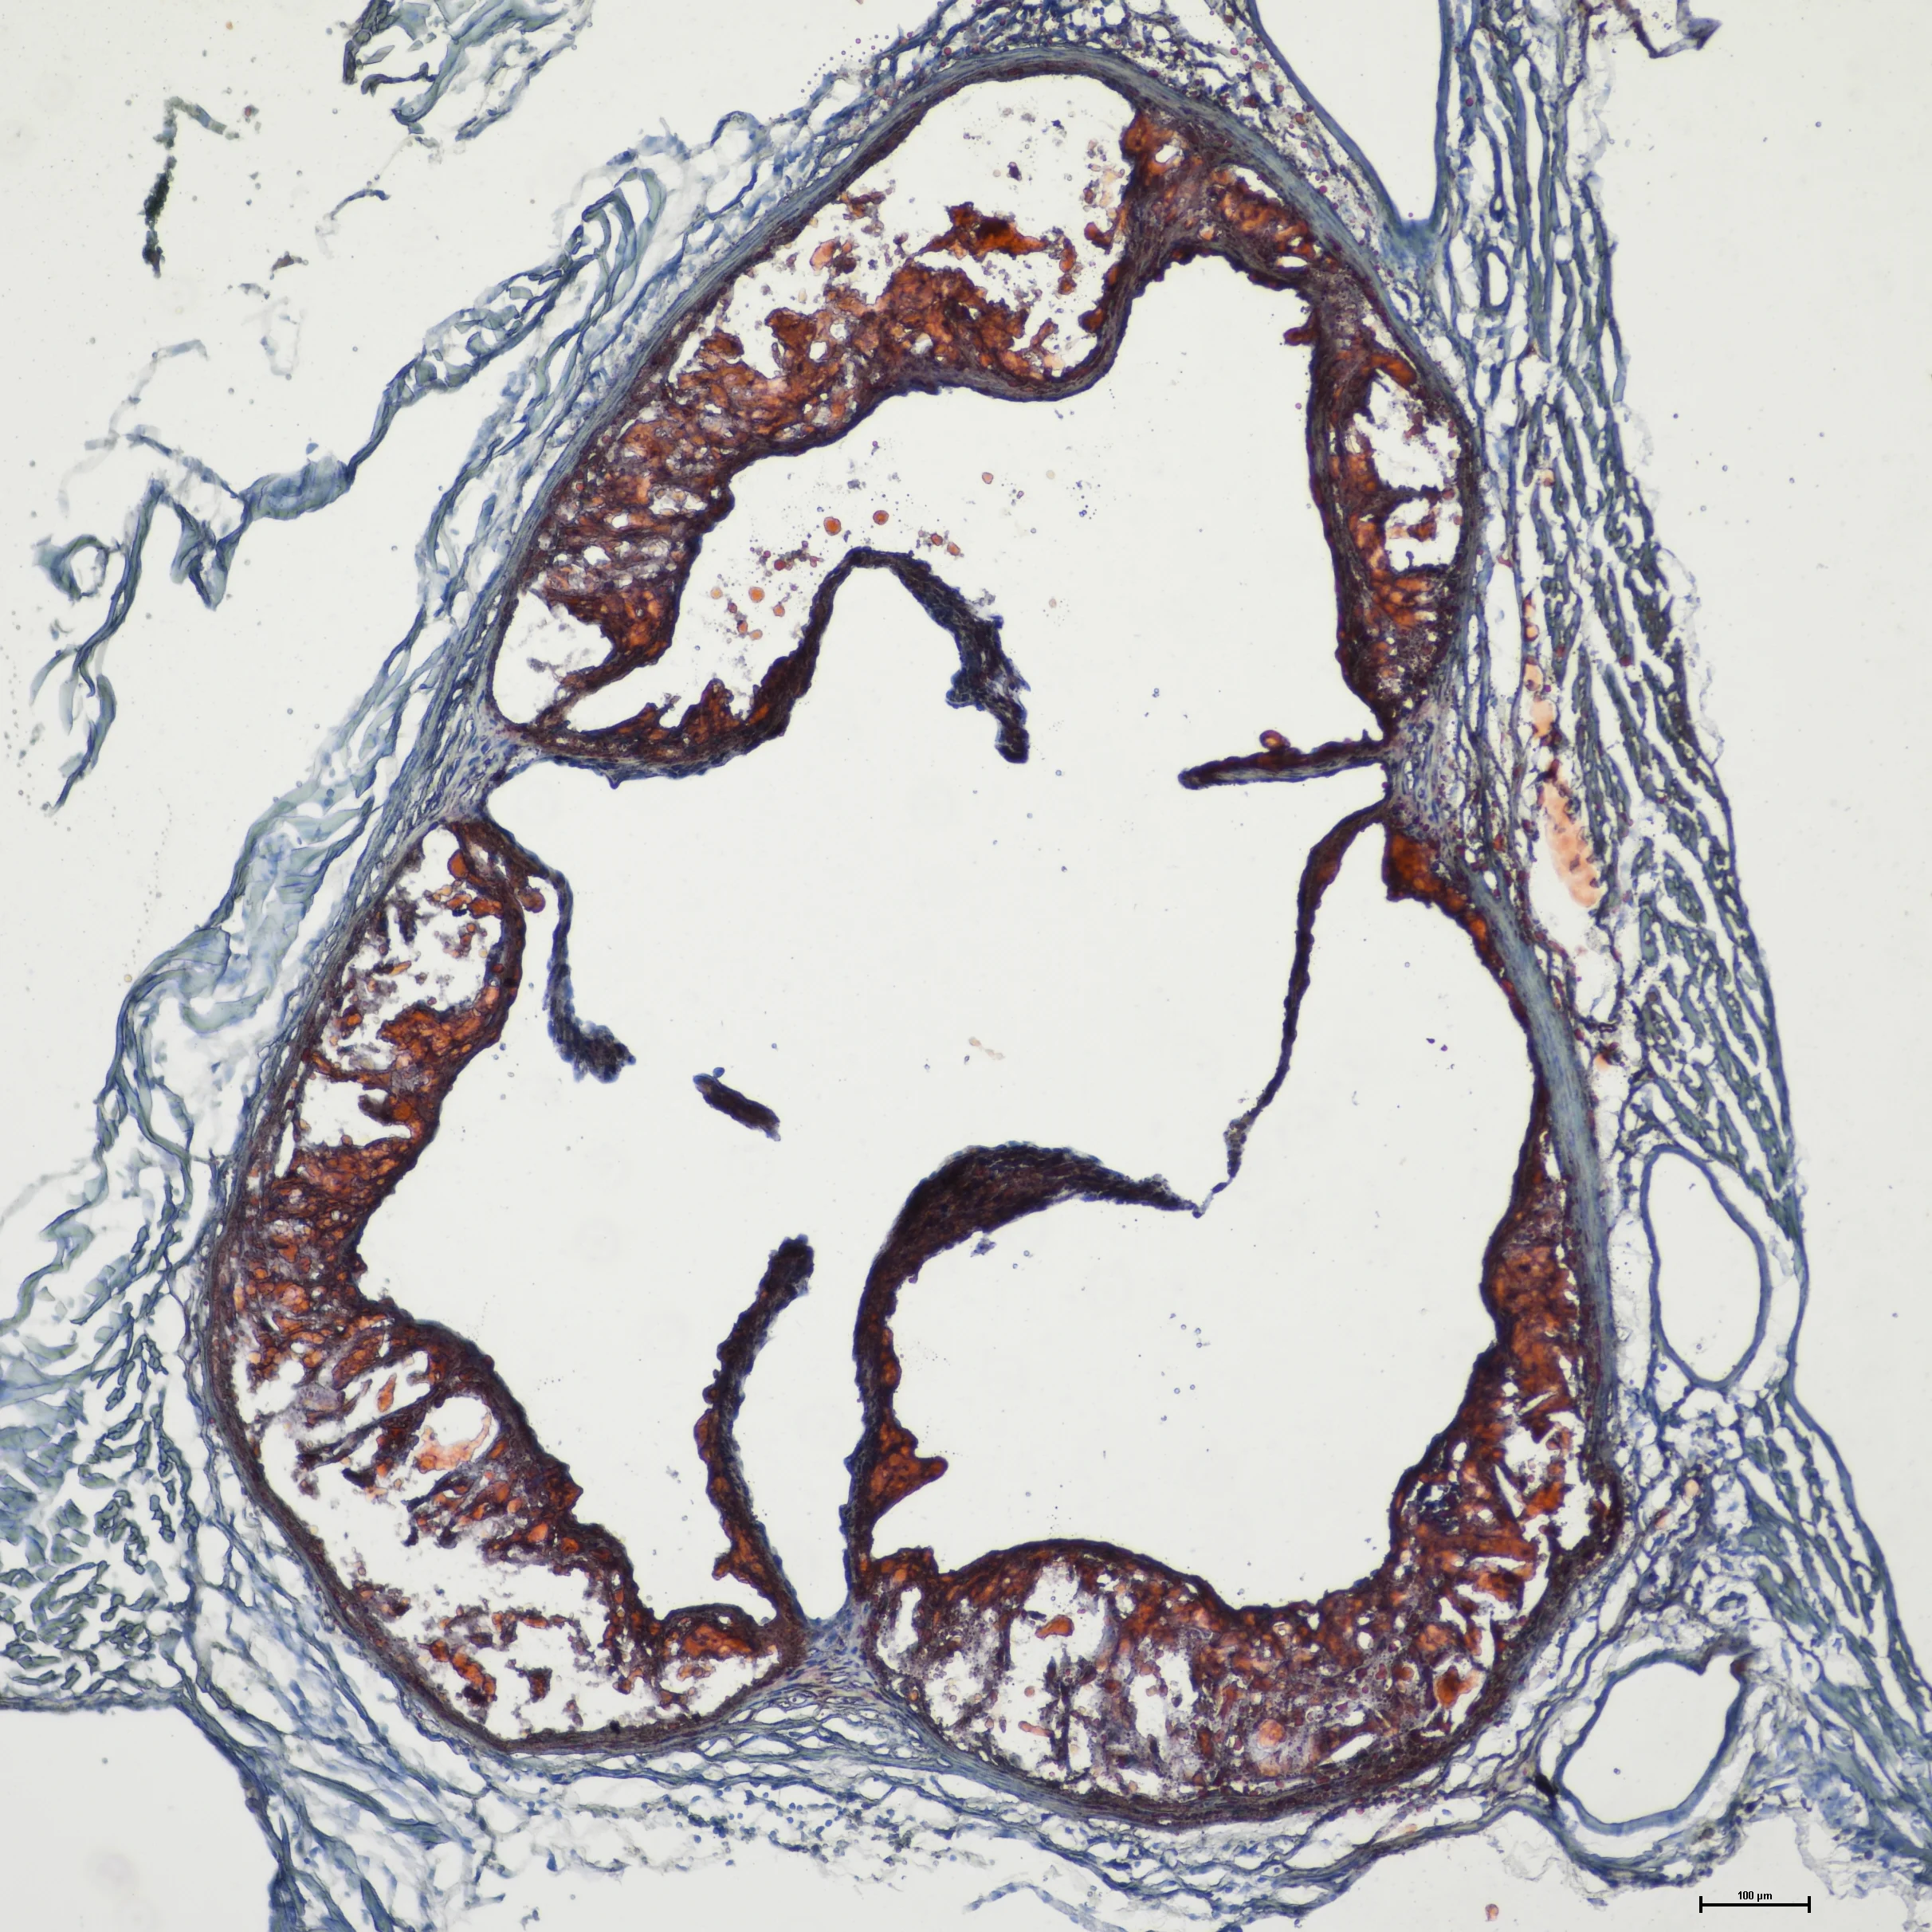

Macrophage accumulation in tissues promotes disease. Left: Tumor-associated macrophages in early TNBC tumors. Middle: Macrophages forming crown-like structures in obese adipose tissue. Right: Macrophages engulf cholesterol to form foam cells in artery wall plaques.